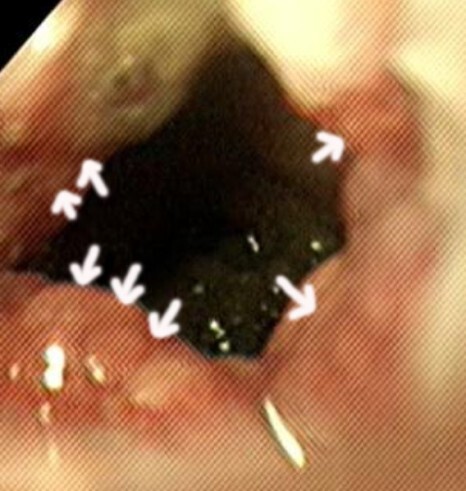

시술 이후 내시경 검사에서 협착 부위에 약간의

출혈이 확인되었지만 수지검사상 협착 부위가

확인되지 않는 것을 확인 후 시술을 종료하였습니다.